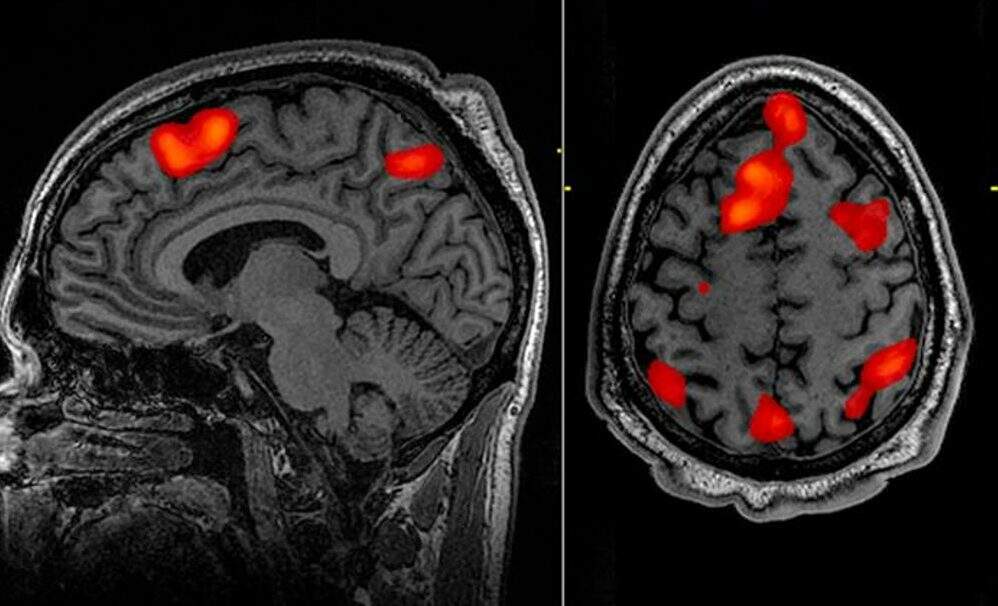

Enquanto um grupo de neurocientistas avaliava um paciente de 87 anos com epilepsia, o idoso acabou sofrendo um ataque cardíaco e morreu. Diante do resultado inesperado, foram obtidos dados inéditos de como o cérebro se comporta na hora da morte, e o que impressionou os pesquisadores foi a indicação de que lembranças da vida são resgatadas nos últimos momentos de vida. Tal percepção foi revelada por padrões de ondas rítmicas semelhantes às que são registradas durante o sono ou a meditação.

A ondas cerebrais do tipo gama mencionadas por Zemmar são referentes a funções altamente cognitivas, relacionadas à concentração, sonhos, meditação, recuperação de memória e processamento de informações. Por isso, o cientista avalia que o cérebro pode reproduzir uma última lembrança de eventos importantes da vida pouco antes da morte através da geração de tais oscilações.